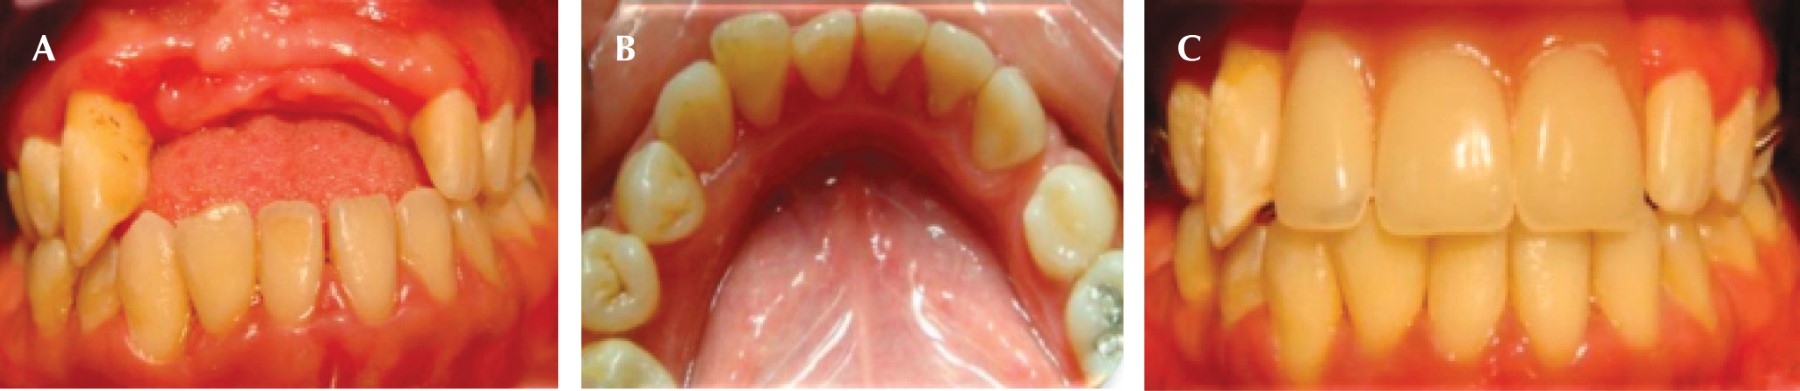

A la inspección clínica se observa agrandamiento gingival en la zona anterior superior (Figura 1A), múltiples abscesos periodontales (Figura 1B), presencia de biofilm microbiano, cálculo supragingival y subgingival. Durante el examen periodontal se encontraron profundidades al sondaje de 5, 7 y hasta 13 mm y movilidad grado II, en la evaluación radiográfica se observó reabsorción ósea generalizada (Figura 1C y D).

Una vez establecido el diagnóstico, se emitió el plan de tratamiento que consistió en realizar una fase I periodontal, alternando sus citas con el Hospital "Dr. Manuel Gea González" para el control de su glicemia. Después de modificar el tratamiento para la diabetes por parte del Hospital y realizando el control mecánico del biofilm microbiano, se comenzaron a observar cambios clínicos, como disminución del aumento de volumen (Figura 2A y C) y desaparición de los absceso periodontales (Figura 2B y D). Una vez que los niveles de glucosa se estabilizaron, se inició la fase II del nivel de tratamiento periodontal (extracciones, desbridamiento por colgajo con injerto óseo), se medicó a la paciente con doxiciclina (previo al procedimiento quirúrgico una cápsula de 100 mg cada 12 horas, segundo día hasta el séptimo día, una cápsula de 50 mg cada 12 horas) y ketorolaco de 10 mg, una tableta cada ocho horas o sólo en caso de dolor. Después de estabilizar periodontalmente a la paciente se incorporó a la terapia de mantenimiento y se dio inicio el tratamiento de rehabilitación, elaborando una prótesis parcial removible (Figura 3A-C). Después de dos años de adhesión al tratamiento, la paciente dejó de asistir a consulta.